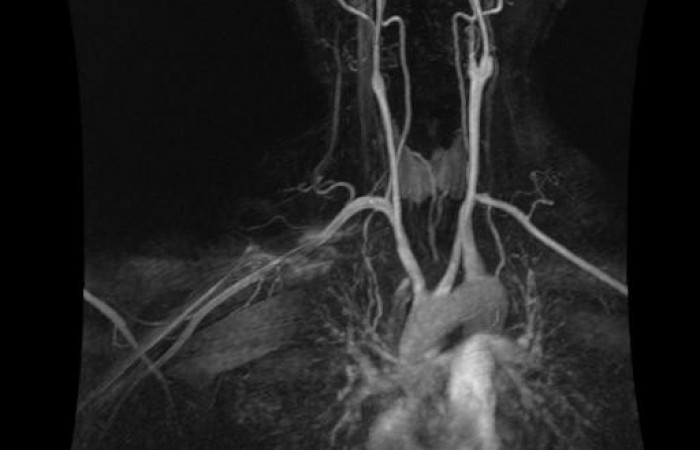

ˇ angiografia bez środków kontrastowych

ˇ angiografia z podaniem środków kontrastowych (ze strzykawki automatycznej)

ˇ angiografia obwodowa z podaniem środka kontrastowego (strzykawka automatyczna, automatyczny przesuw stołu)

ˇ angiografia obwodowa bez podania środka kontrastowego